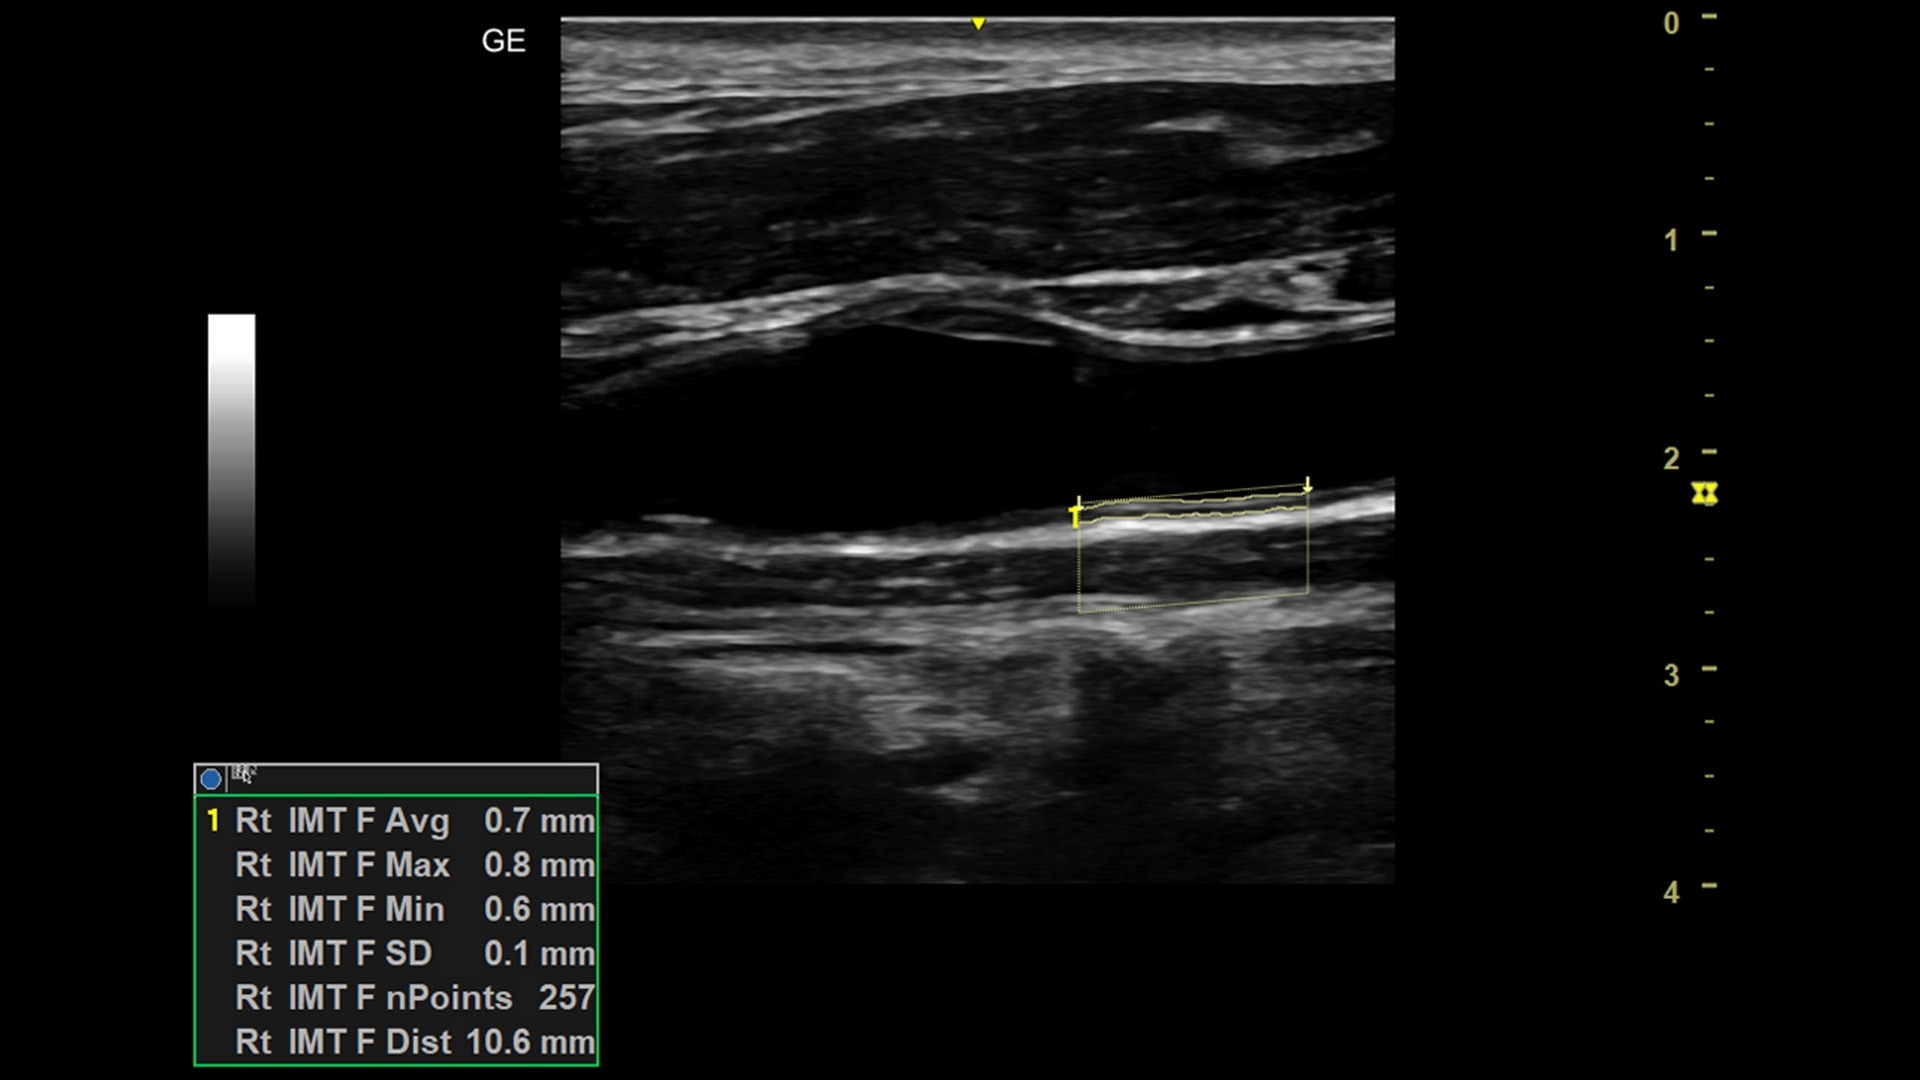

Competent

Delivering peace of mind through world-class imaging quality